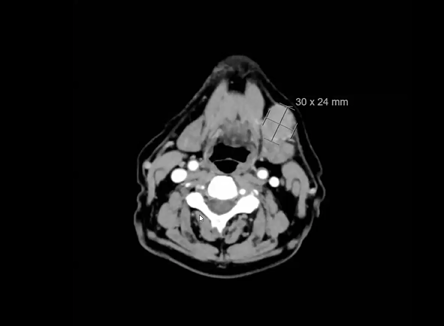

nasopharynx, MRI, PET, CT, NPX carcinoma, balloon procedure, right nasal pharyngeal carcinoma, 2A node, microscopic disease, T1, CLL, right parotid mass, squamous cell, right superficial parotidectomy, modified neck dissection, right temporal skin lesion excision, lymph node, ECE, bolus, dissecte...